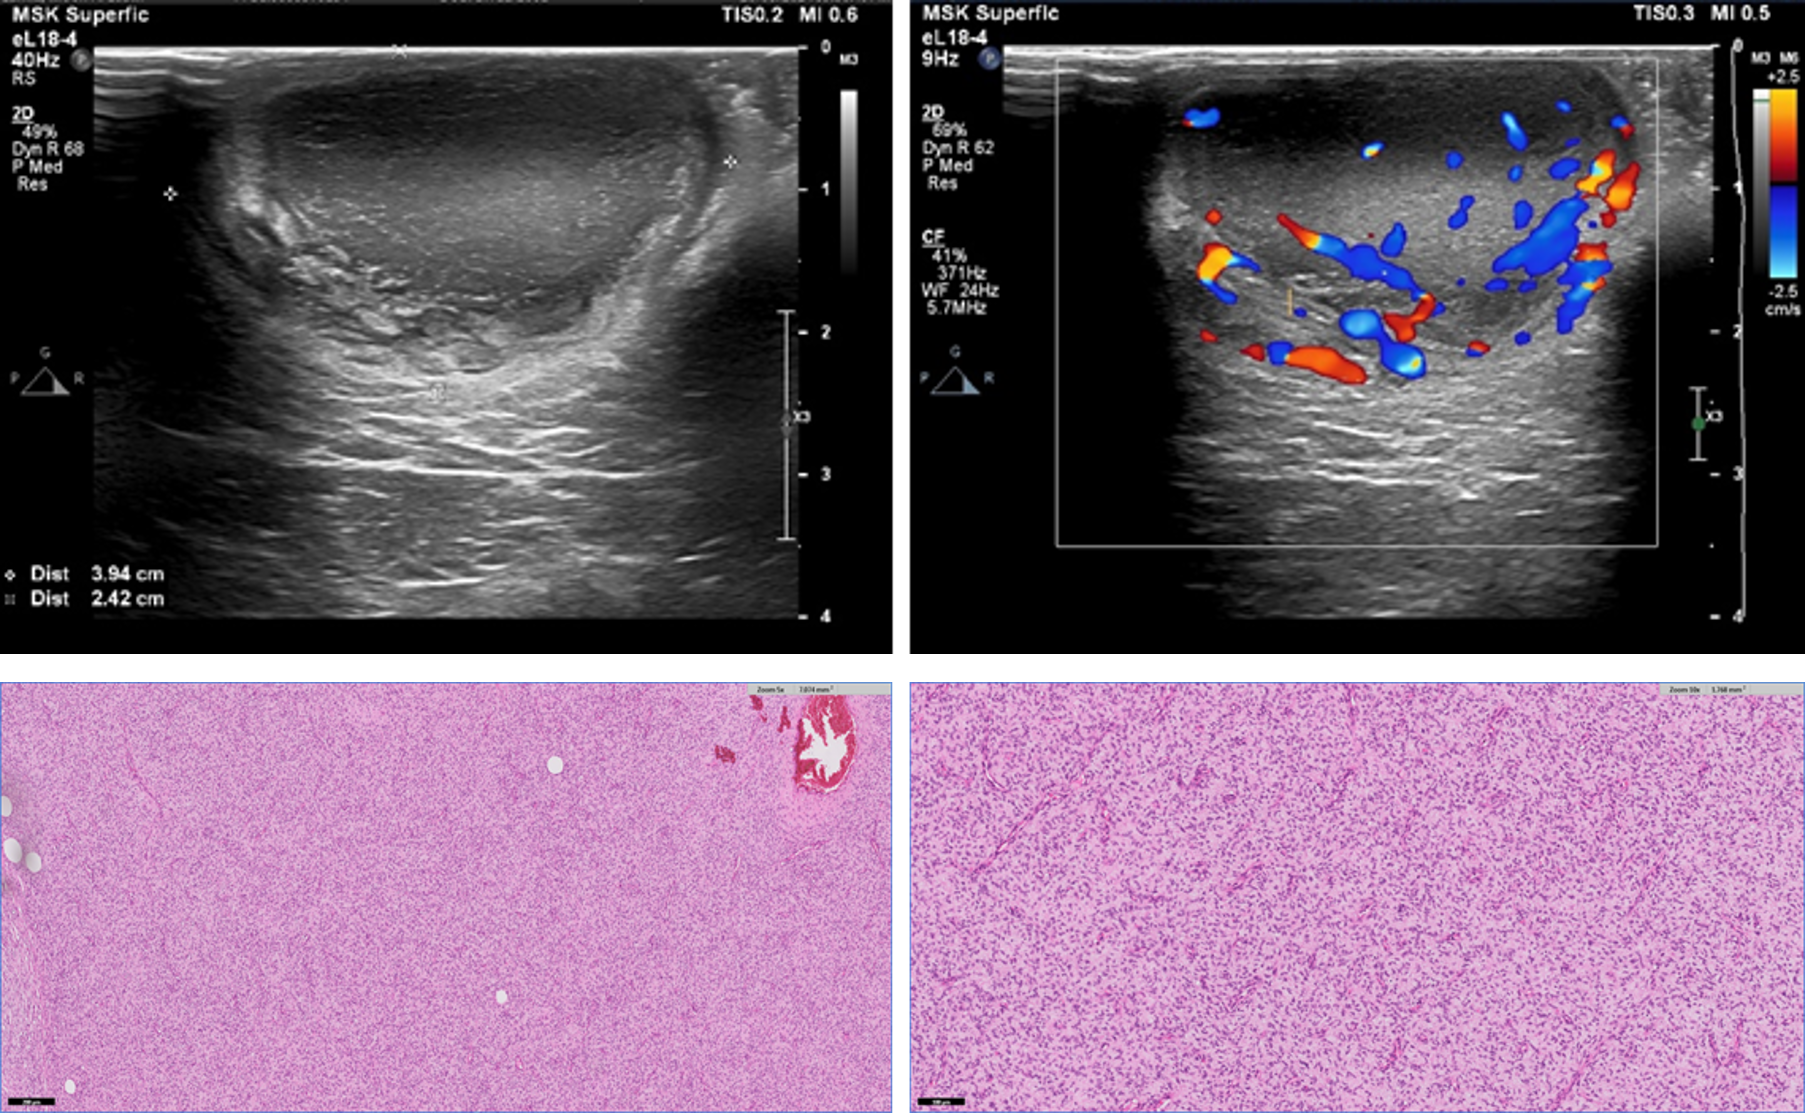

Primary T-Cell Lymphoma of the Prostate in a Dog – Case Report

Marina Laudares Costa, Carlos Eduardo Fonseca-Alves, Gustavo Garkalns de Souza Oliveira, Ana Paula Massae Nakage-Canesin, Paula Christine Bonadio Rezende, Thiago Demarchi Munhoz